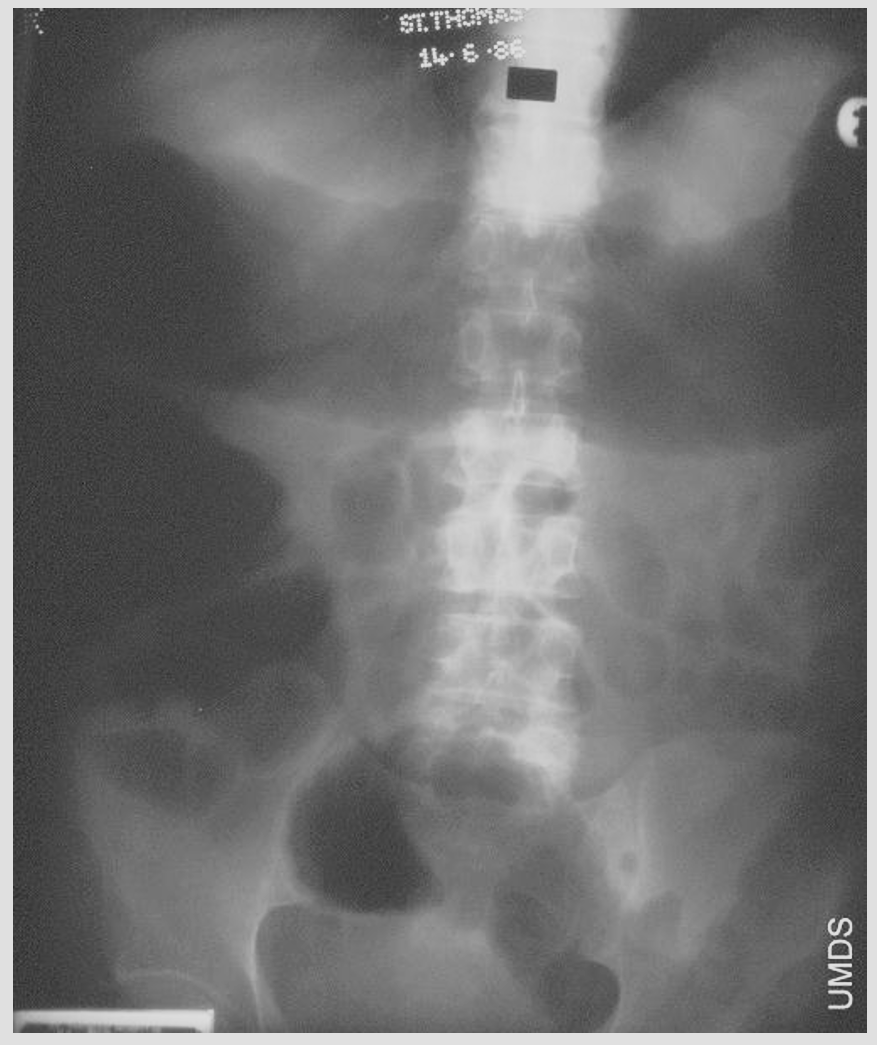

What is this ?

Ulcerative colitis plain Xray

1) Stool absent in inflammed colon

2) Mucosal oedema / ‘thumb-printing’

3) Toxic megacolon:

-Transverse >5.5cm

-Caecum >9cm